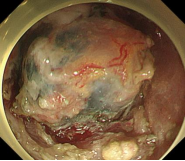

直肠巨大侧向发育型肿瘤,内镜下完整切除(ESD),术后病理证实粘膜内癌,不需追加治疗,达到治愈目的,保留正常器官,避免外科手术。

胃内4x4cm粘膜下隆起,胃镜下完整切除(ESE),术后病理证实平滑肌瘤,保留胃正常组织结构。

结肠腺瘤的ESD手术

内镜手术展示